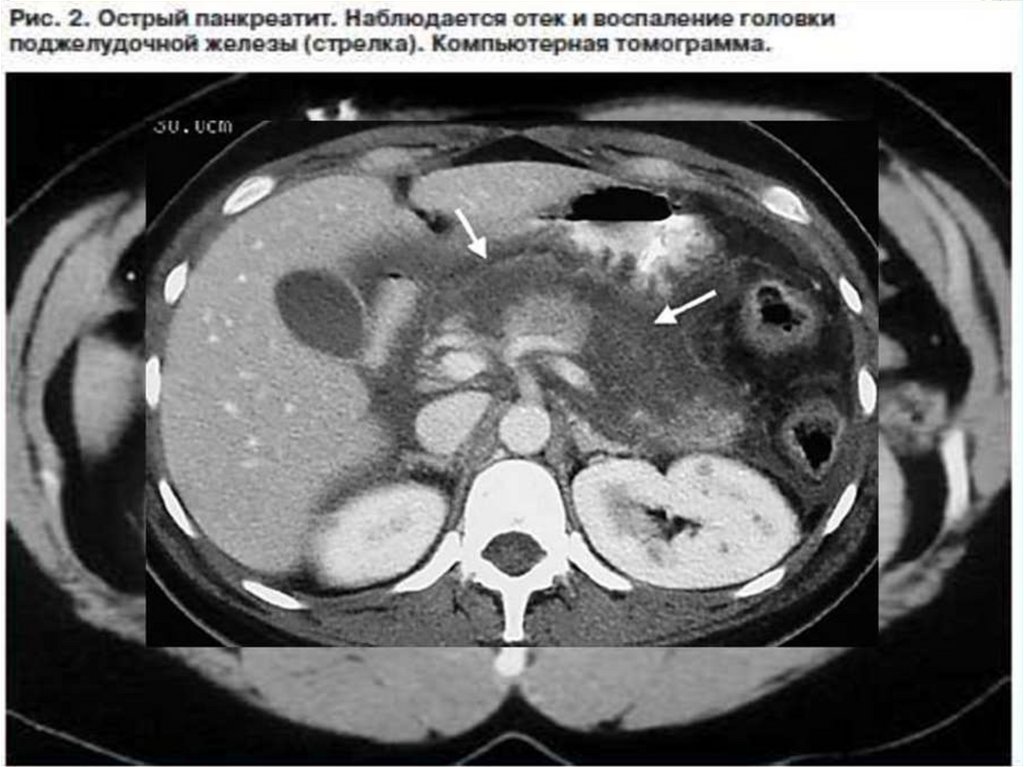

ОСТРЫЙ ПАНКРЕАТИТ